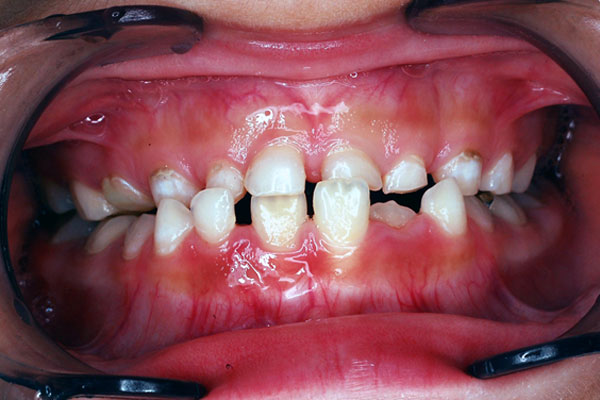

7才9ヶ月時点で大人の歯も反対咬合(受け口)になりました。2つ目を開始します。

前歯をネジの力で押し出して、角度を変える取り外し式の装置に変更します。